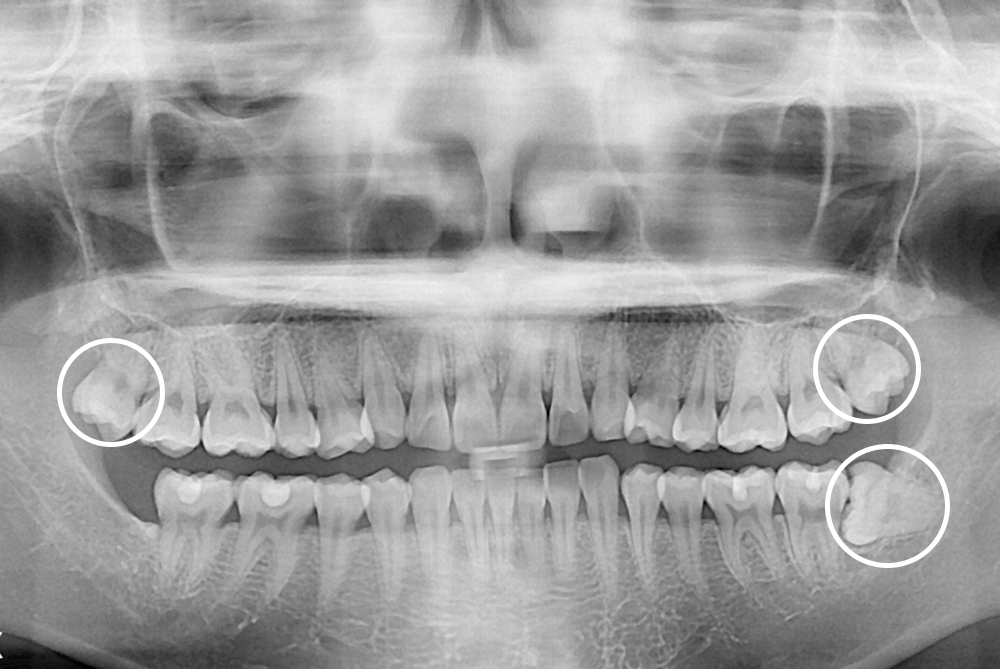

[사랑니] 매복 사랑니 발치

치료전 : 2020-02-26